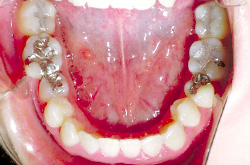

上あご・正面・下あご

before

after